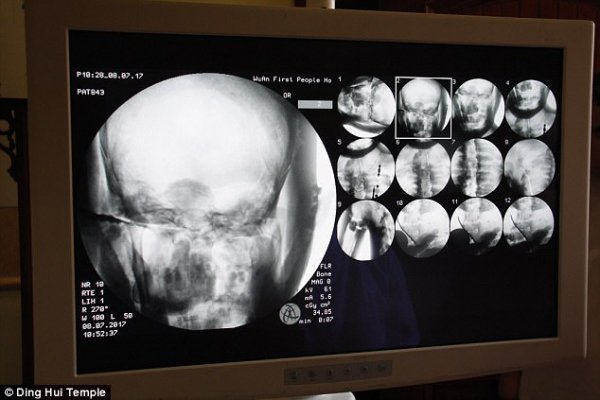

但是經過千年大家才知道這尊佛像裏頭的卻是....根據了解有研究學者透過X光還有XT掃描檢驗,發現驚人的秘密!這是貨真價實的木乃伊,但沒想到最難保存的大腦竟然都還留著!?

當地學者受訪表示:「我們在掃描後發現,他的骨頭跟一般人的一樣完整。」

「上額、上面的牙齒、肋骨、脊椎骨、連關節全部都還在。真的是很驚奇的景象」